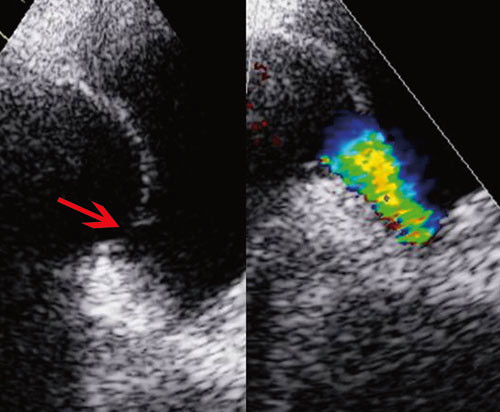

Siden hypoksemien kunne være utrykk for at blodet ble shuntet fra venøst til systemisk kretsløp, ble det injisert agitert saltvannsoppløsning (luftmikrobobler) i perifer vene. Umiddelbar påvisning av «kontrast» i venstre atrium antydet at det var en stor kontrastpassasje på forkammernivå (fig 1). En slik shunting av venøst blod til venstre hjertekammer kunne forklare pasientens hypoksemi og tungpust. For å kartlegge årsaksforholdene nærmere ble det utført transøsofageal ekkokardiografi da denne metoden gir høyere bildeoppløsning. Undersøkelsen avdekket et åpent (patent) foramen ovale (fig 2).

Hyppigheten av åpent foramen ovale i normalbefolkningen er 25 – 30 % (2, 3). Ved normale trykkforhold i hjertet vil åpent foramen ovale ikke medføre betydelig grad av shunting av venøst blod (4). Vår pasient hadde flere ekkokardiografiske tegn på trykk-volum-belastning av høyre hjertehalvdel: venestuving, dilatert v. cava, V-bølge, bukende atrieseptum og høye antegrade hastigheter over trikuspidalostiet. Derfor ønsket man bedre visualisering av trikuspidalklaffen.

I en noe uortodoks projeksjon fremkom det at trikuspidalinsuffiensen var stor (grad 3 – 4/4). Trikuspidalklaffens seil var fortykket, korte og lite mobile. Klaffeseilene sto i halvåpen posisjon i systolen når de skulle være lukket. De påviste forandringene i trikuspidalapparatet ga mistanke om karsinoid hjertesykdom. Ved å plassere ultralydhodet under kostalbuen kunne leveren visualiseres. Leveren var inhomogen med multiple ekkotette lesjoner, slik at mistanken om karsinoid sykdom ble ytterligere forsterket (fig 3).